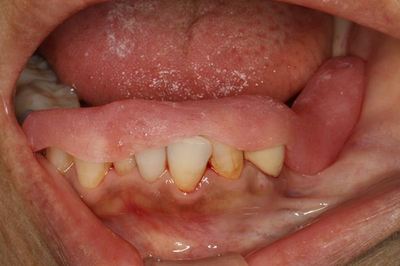

ミラー像

左下奥歯の部分にインプラント治療をします。

骨の陥没がありますので事前にCTで検査します。

(写真はオペ直前のものです。)